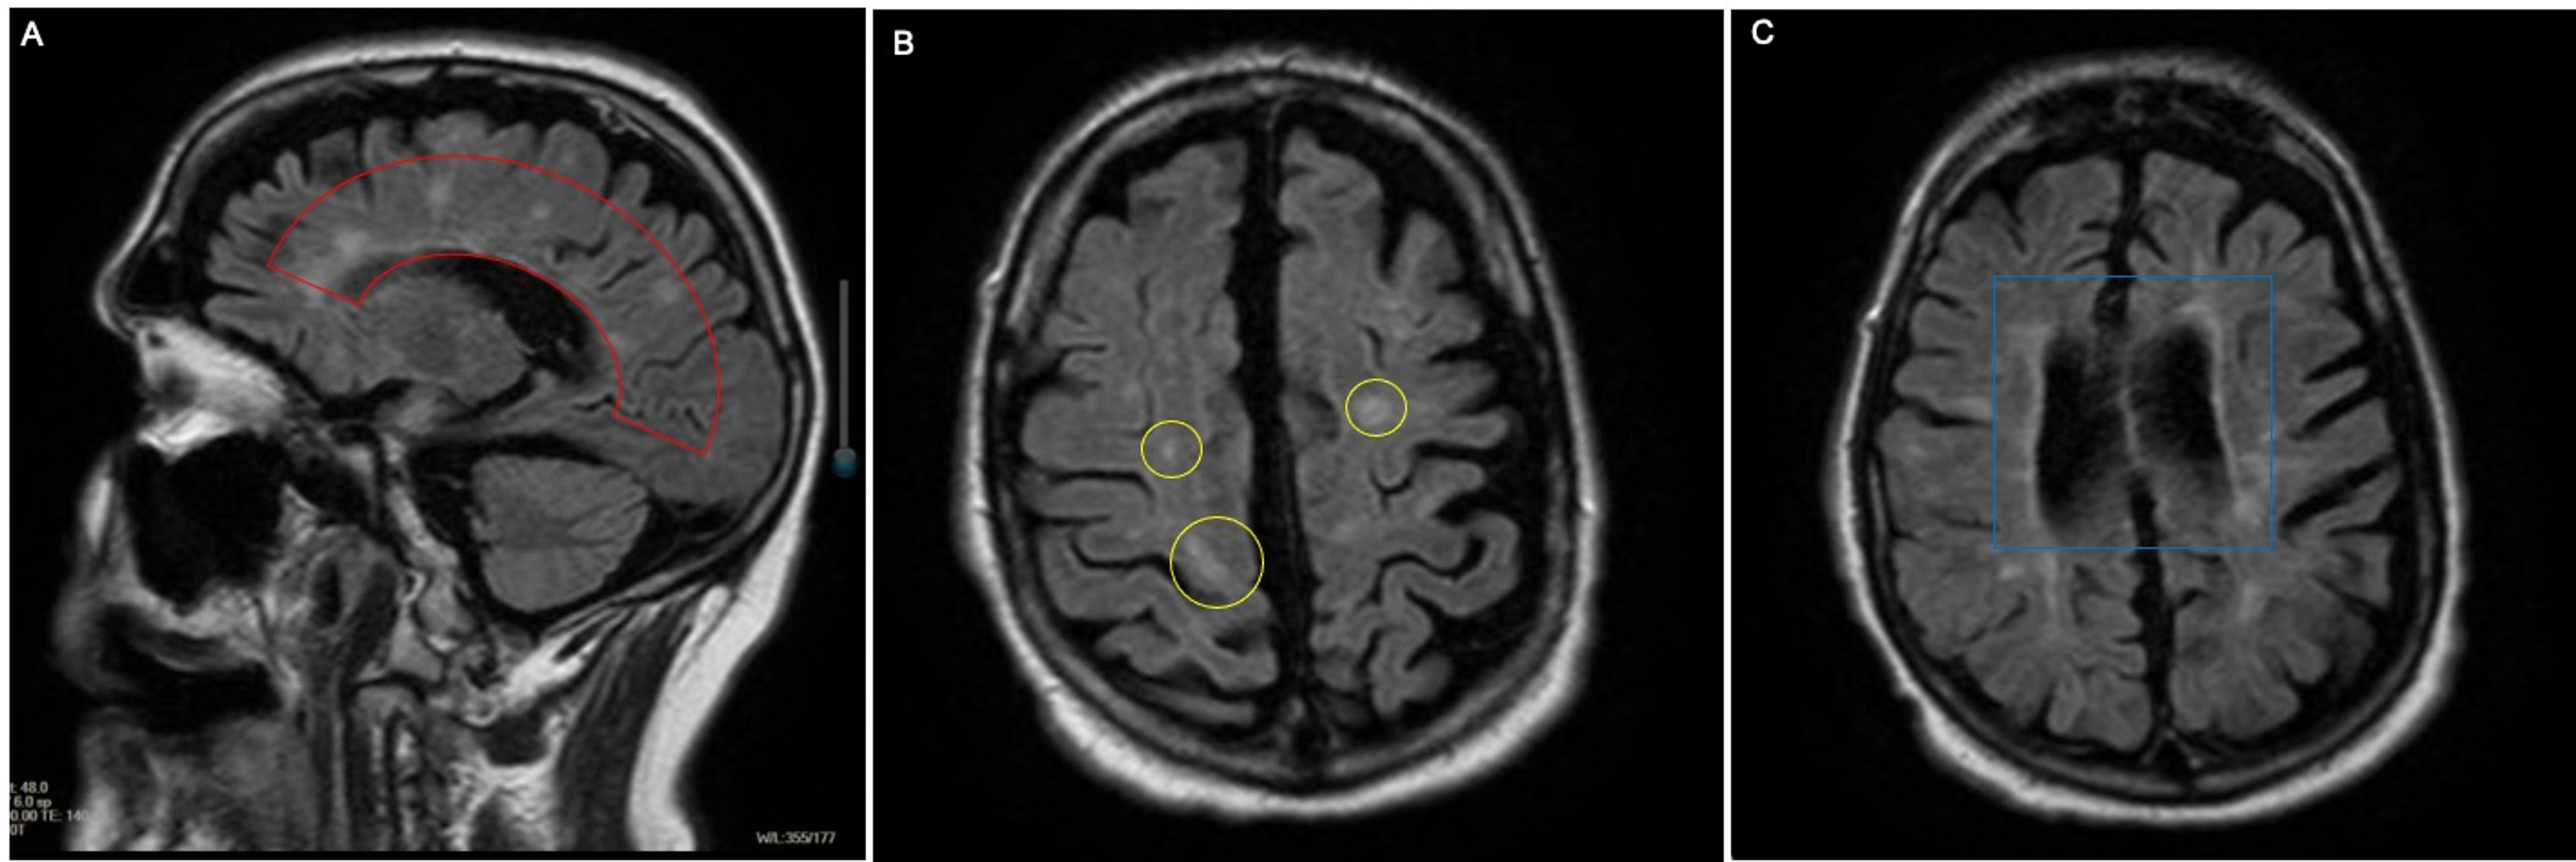

Magnetic resonance imaging MRI was formally included in the diagnostic work-up of patients presenting with a clinically isolated syndrome CIS suggestive of multiple sclerosis MS in 2001 by an International Panel of experts. In an attempt to assure the highest sensitivity and specificity a set of guidelines referred to as the McDonald criteria 1 utilizes magnetic resonance imaging MRI to provide supportive data to facilitate the diagnosis of MS. However if there is inflammation that reduces the BBB the contrast is able to get into the brain and will show up as actively enhancing on inflammed lesions.

Its thought to be the result of an immune system attack. Examining the results from an MRI a spinal tap blood tests and evoked potentials measurements of electrical activity in certain areas of the brain and spinal cord against the McDonald criteria help doctors discern between MS and other diseases that can. 1 MS diagnosis requires demonstration of disease dissemination in space DIS and time DIT and exclusion of other conditions that can mimic.

Which type of ms is the most common type of the disease relapsing. Magnetic resonance imaging MRI plays a crucial role in multiple sclerosis MS diagnosis disease monitoring prognostication and research. The MRI can also be used to confirm that damage has occurred at two different points in time.

In one study 35-mm axial T2-weighted images with full spinal cord coverage showed 22 more lesions in patients with MS than 3-mm sagittal scans especially for lesions with small axial diameters. The MRI can be used to look for a second area of damage in a person who has experienced only one attack also called a relapse or an exacerbation of MS-like symptoms referred to as clinically-isolated syndrome CIS. MRI has been part of the International Panel criteria for the diagnosis of MS since 2001 and its use has become increasingly vital as.

8 Barkhof criteria were not designed to be applied to patients without suspicion of MS. It is the preferred imaging method to help establish a diagnosis of MS and to monitor the course of the disease. MS lesions can show white matter inflammation demyelination and scarring or sclerosis.